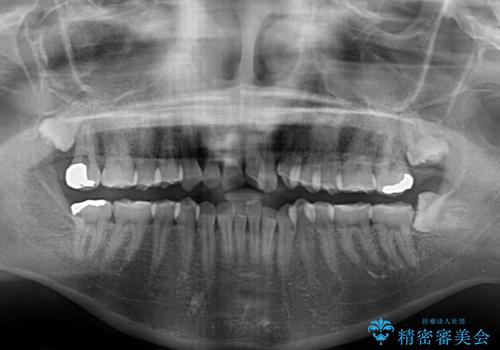

- 前歯のデコボコとクロスバイトが気になり、インビザラインによる矯正治療を希望して来院された患者様です。

上顎側切歯(上の真ん中から2番目の歯)が舌側転位している場合、無理して動かそうとすると歯髄壊死を起こすリスクが高い印象があります。

インビザライン単体でも治療は可能ですが、安全策としてインビザラインで歯列を移動する前に上顎前歯をワイヤー矯正で整え、その後上下歯列をインビザラインにて矯正治療を行うこととしました。

舌側転位している側切歯特有の、切縁の位置が不揃いであったり、根元が内側に引っ込んだ状態であったりという、インビザライン独特の仕上がりになることなく、きれいに整った歯列とすることができました。